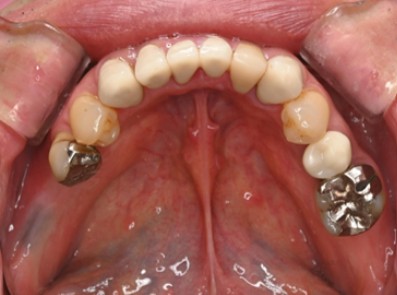

3ヶ月後

ジルコニアインレー装着と最終クラウン装着を同時におこなった。咬合調整

機能・審美ともに良好で治療完了

隣在歯の形態回復により、咬合安定。

患者さんは「左右どちらでも噛めるようになり、食事が楽しくなった」と笑顔で報告。

硬いものも安心して噛めるようになり、「お肉が美味しく感じる」との感想が印象的でした。

また、金属冠をジルコニアに置換することで審美性と清掃性が向上し、咬合関係の修復、全体の口腔内環境も改善しました。